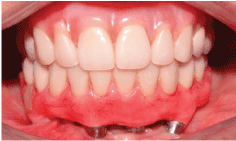

Figure 1: Clinical situation of the patient at the first visit, where the lack of implants can be observed in the posterior region of the mandible on the left side.

During the visit, an increase in volume was observed in the posterior region of the mandible on the right side and mobility in the region of the most distal implant, where it was impossible to diagnose whether the mobility was from the implant or resulting from the mandibular fracture (Figure 1). After the images were examined, a radiolucent line was observed beginning at the crest of the flap and continuing to the basal at the implant, characterizing a mandibular fracture without detachment of fragments. It was also possible to observe that this was a mandible with little bone height and the other implants revealed marginal bone loss with the exception of one (Figures 2 and 3).